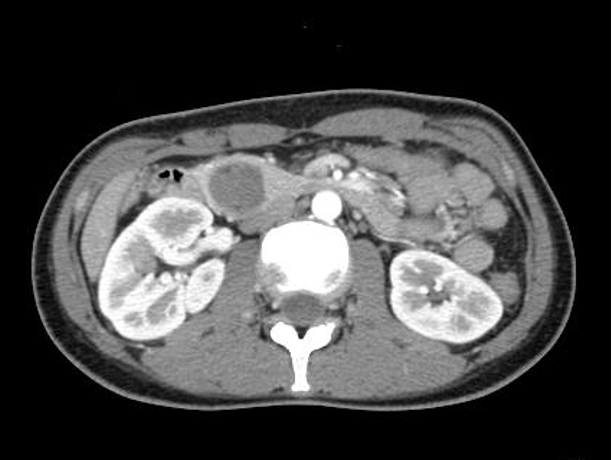

精査・加療目的に大学病院を受診し、造影腹部CTで膵頭部に腫瘍が確認されたため、超音波内視鏡検査目的に当院を紹介受診されました。

腹部CT検査では、膵頭部に2cm大の類円形腫瘍があり、内部に造影効果のある部位も認めます。

<腹部CT>

腫瘍の壁は一部、石灰化(矢印)しています。

<腹部CT>

CT所見からは、膵充実性偽乳頭腫瘍、膵神経内分泌腫瘍などが疑われました。